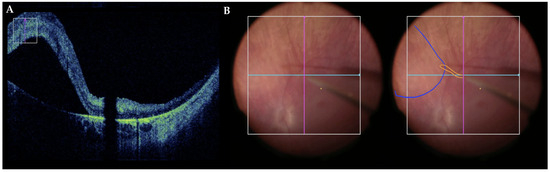

- Gregori, N.Z.; Lam, B.L.; Davis, J.L. Intraoperative Use of Microscope-Integrated Optical Coherence Tomography for Subretinal Gene Therapy Delivery. Retina 2019, 39, S9–S12. [Google Scholar] [CrossRef]

- Maierhofer, N.A.; Jablonka, A.-M.; Roodaki, H.; Nasseri, M.A.; Eslami, A.; Klaas, J.; Lohmann, C.P.; Maier, M.; Zapp, D. IOCT-Guided Simulated Subretinal Injections: A Comparison between Manual and Robot-Assisted Techniques in an Ex-Vivo Porcine Model. J. Robot Surg. 2023, 17, 2735–2742. [Google Scholar] [CrossRef] [PubMed]

- Zhang, P.; Kim, J.W.; Gehlbach, P.; Iordachita, I.; Kobilarov, M. Autonomous Needle Navigation in Subretinal Injections via IOCT. IEEE Robot Autom. Lett. 2024, 9, 4154–4161. [Google Scholar] [CrossRef]

- Dehghani, S.; Sommersperger, M.; Zhang, P.; Martin-Gomez, A.; Busam, B.; Gehlbach, P.; Navab, N.; Nasseri, M.A.; Iordachita, I. Robotic Navigation Autonomy for Subretinal Injection via Intelligent Real-Time Virtual IOCT Volume Slicing. In Proceedings of the 2023 IEEE International Conference on Robotics and Automation (ICRA), London, UK, 29 May–2 June 2023; IEEE: New York, NY, USA, 2023; pp. 4724–4731. [Google Scholar]

- Arikan, D.; Zhang, P.; Sommersperger, M.; Dehghani, S.; Esfandiari, M.; Taylor, R.H.; Nasseri, M.A.; Gehlbach, P.; Navab, N.; Iordachita, I. Real-Time Deformation-Aware Control for Autonomous Robotic Subretinal Injection under IOCT Guidance. arXiv 2024, arXiv:2411.06557. [Google Scholar]